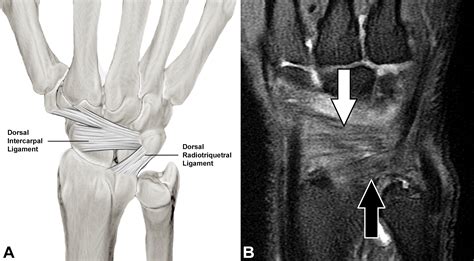

• Ligament and Tendon Injuries: Tears or strains in the ligaments and tendons can be clearly visualized with MRI.

Interpreting MRI wrist joint scan results requires expertise in radiology. The radiologist will review the images and provide a report detailing any abnormalities or conditions detected. The report will include:

• Description of Findings: A detailed description of any abnormalities, such as fractures, tears, or cysts.